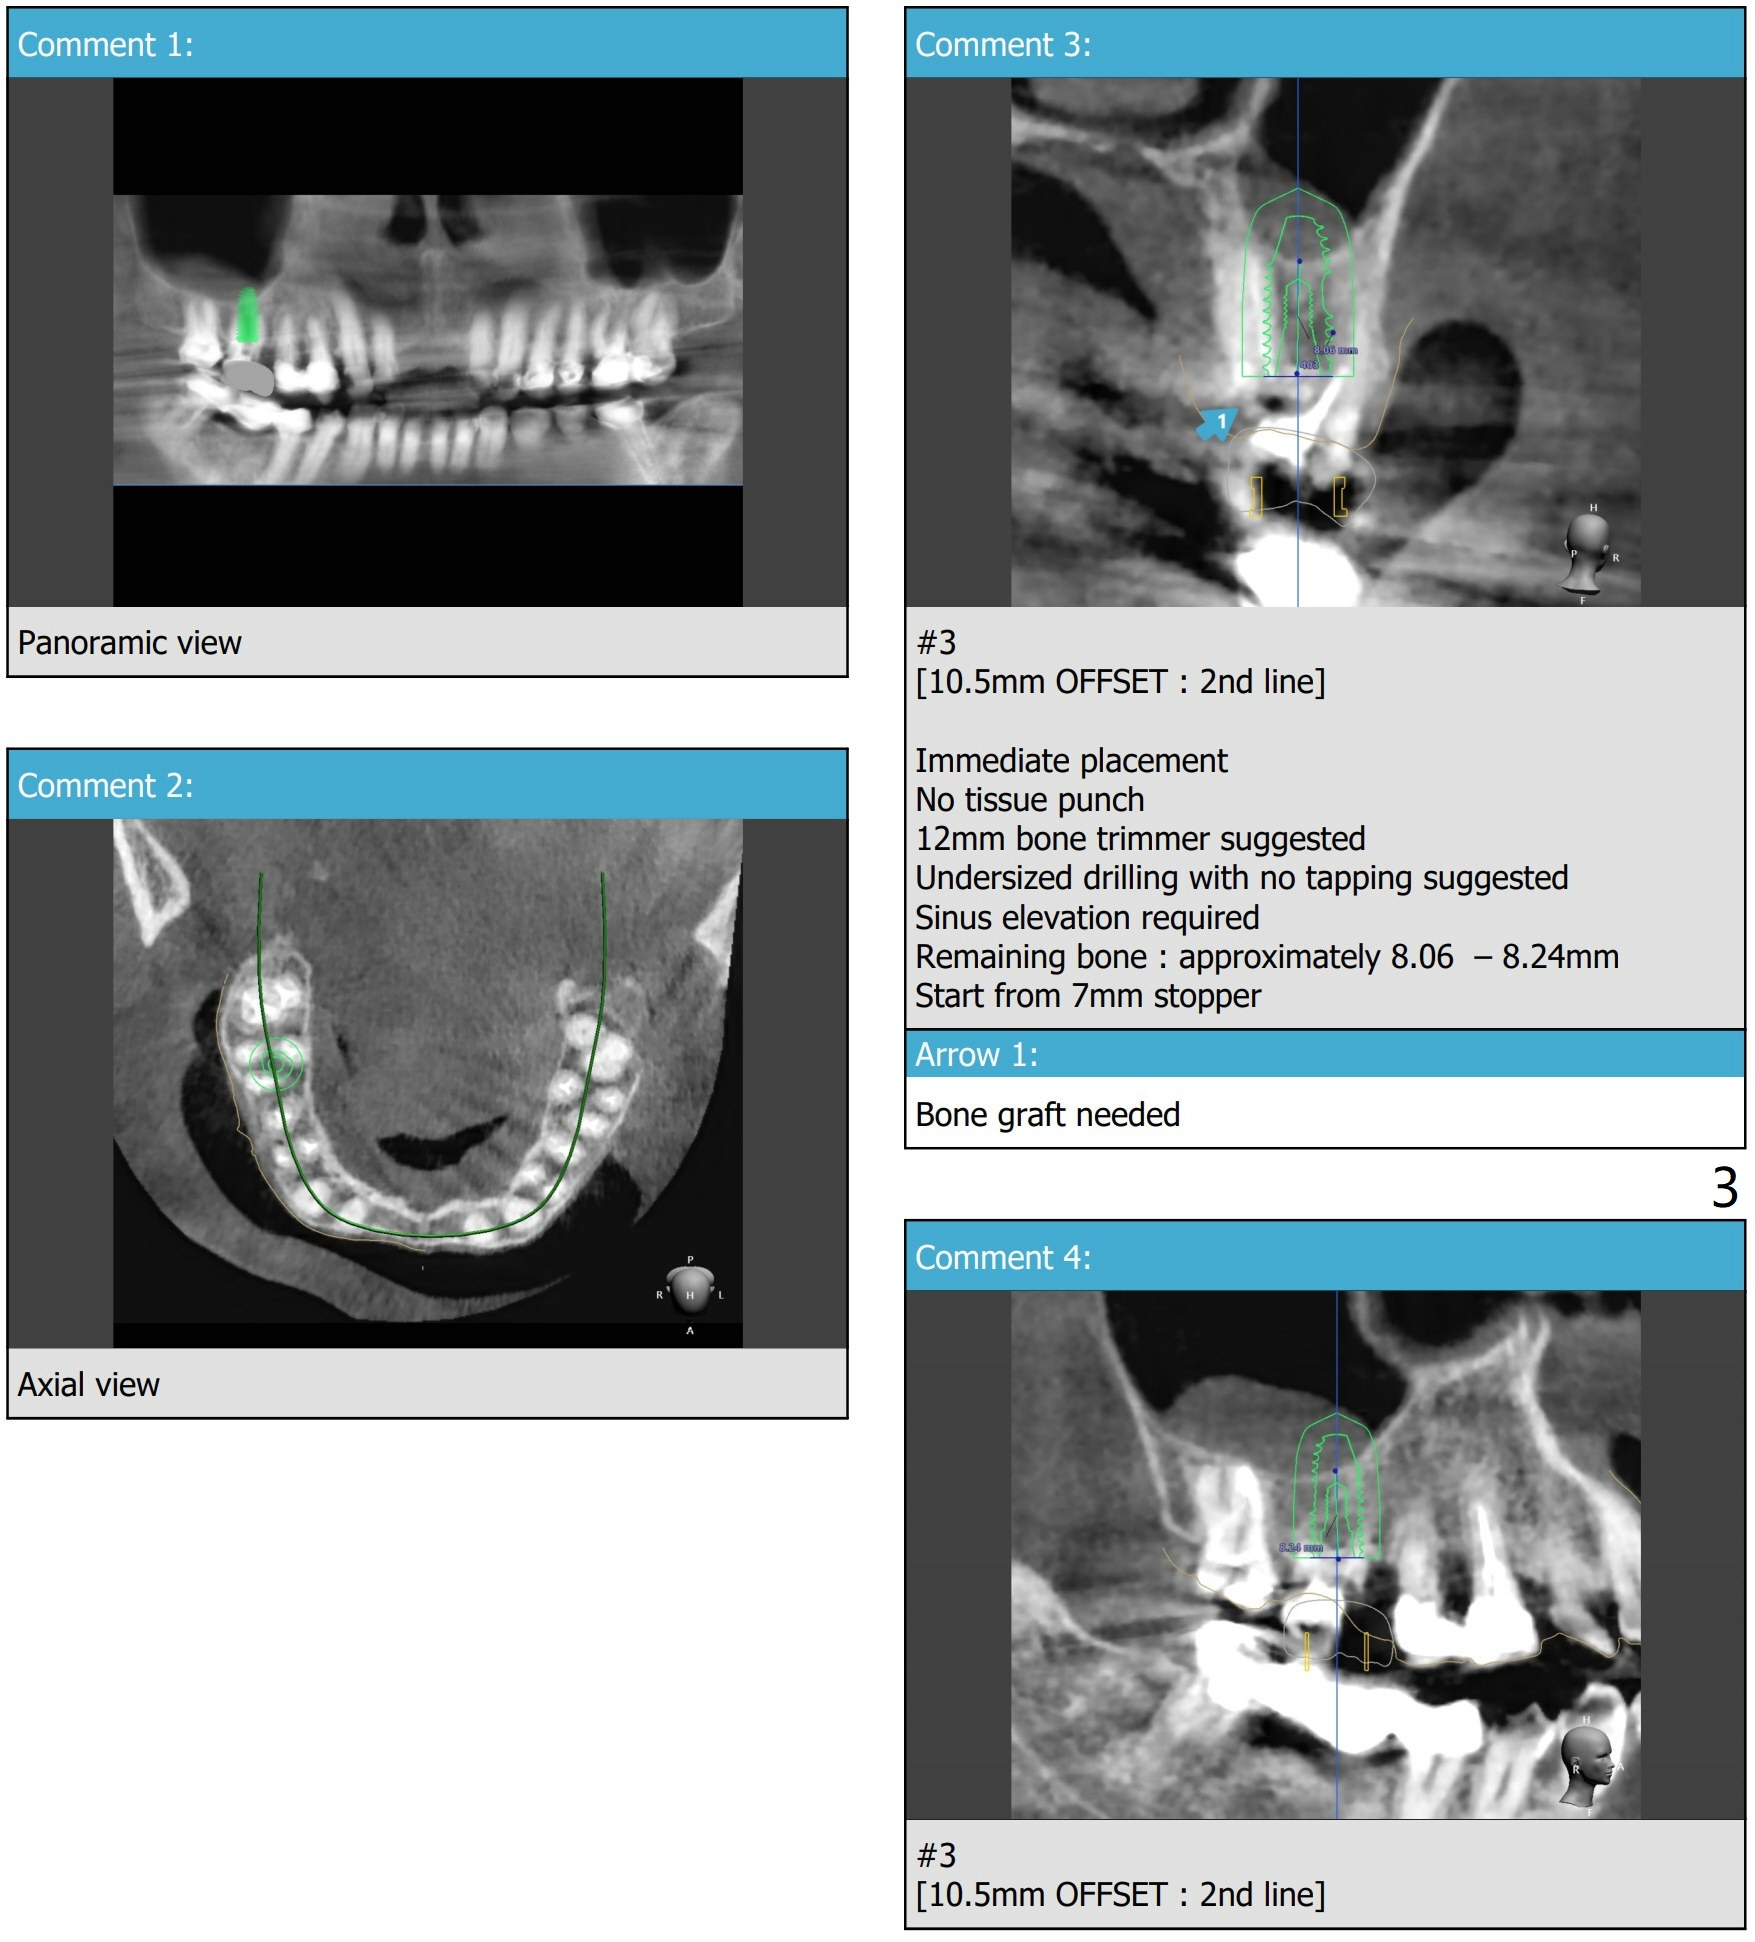

Use 5x10 mm Dummy Implant for Sinus Lift ~1.5 mm short of 1st line

A 67-year-old woman has dislodged #3 and #2 crowns. The former is lost, while the latter is short. The tooth #3 has severe bone loss. After immediate implant and immediate abutment, consider splint #2 and 3 temporary crowns for retention.